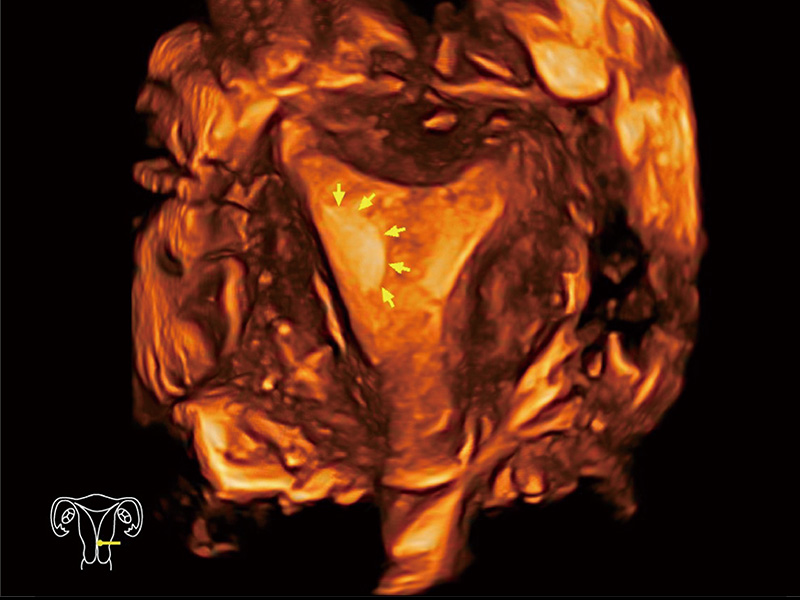

单角子宫